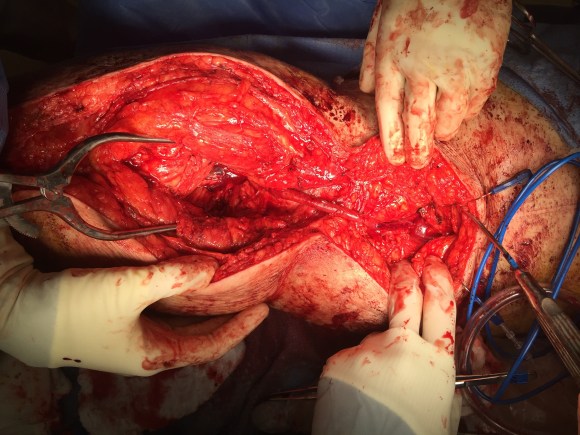

The operation was done in a hybrid suite, as should all limb salvage cases. The retroperitoneal dissection was challenging because of the heavy scar tissue around the well incorporated iliac bypass, but with patience, a clampable 3cm segment was achieved. I am a big fan of Wylie hypogastric clamps because they stay out of the way when placed in a tight narrow spot, and for that same reason, I prefer the Cherry supraceliac aortic clamp. They were designed by my mentor, Ken Cherry, and his mentor, Jack Wylie for this kind of operation. A few venous bleeders were easily handled with my ring compressors (below), and I hope to continue this chain of innovation, but I digress.

The bladder was dissected off the pubis to allow the graft to be tunneled to the right pelvis. A counter incision in the right lower quadrant abdomen and a mid thigh incision mobilizins the anterior compartment muscles to the posterior compartment allowed me to tunnel across the obturator foramen. The obdurator vessels need to be avoided or there will be bleeding. this mid thigh incision allowed exposure of the profunda femoral artery more proximally and allowe the graft to be tunneled anatomically to the below knee popliteal artery for anastomosis. A jump graft was taken off this graft on the thigh to the profunda femoral artery which was small and diseased -no more than 2mm in size. An axillary bypass to this profunda would be doomed to the compromised patency rate published for ax-fem bypasses giving them a bad name. The left superficial femoral artery was exposed and provided outflow to the left iliofemoral bypass which was tunneled far laterally under the inguinal ligament to avoid the scar tissue where the common femoral artery was.

There was immediately multiphasic signal in both feet on release of clamps. After closure of all the incisions and dressings, the right middle toe was amputated.